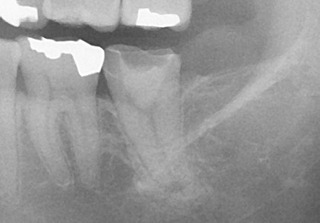

術前のレントゲン 赤丸の部分に病変が見られます。